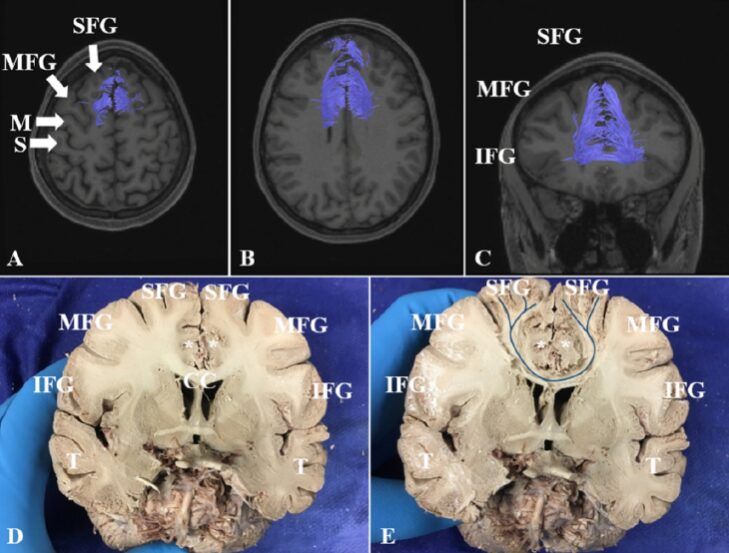

The FAT connects the SFG and the inferior frontal gyrus in the same hemisphere, originating from the upper lateral surface of the SFG just anterior to the precentral gyrus, descending into the deep white matter of the frontal lobe, and then gradually bending approximately 90 degrees posterior-inferiorly, terminating in the opercular and triangular parts of the inferior frontal gyrus (Figure 2). The extent of the FAT extending along the SFG varies among subjects, but no origin of the FAT was found in the frontal pole, nor was it found to originate from the medial cortex of the SFG. It is important to note that the FAT runs deep within the superior longitudinal fasciculus, and carefully removing the superior longitudinal fasciculus is crucial for exposing the FAT in the deep white matter.

Figure 2. Frontal Aslant Tract. A, B: MRI coronal view showing FAT fiber bundle images. C: Lateral structure of the frontal lobe. D, E: FAT from the posterior lateral part of the SFG to the opercular and triangular parts of the inferior frontal gyrus (IFG); the green streamlines in Figure E show the trajectory of the FAT fibers. *: Lateral ventricle; CC: Corpus callosum; IFG: Inferior frontal gyrus; M: Motor center; MFG: Middle frontal gyrus; S: Sensory center; SFG: Superior frontal gyrus; TL: Temporal lobe.